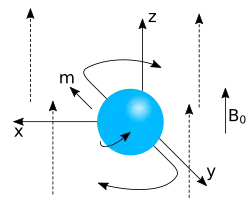

Einige Atomkerne (wie etwa die Wasserstoffkerne) in den Molekülen des zu untersuchenden Gewebes besitzen einen Eigendrehimpuls („Kernspin“) und sind dadurch magnetisch. Diese Kerne erzeugen nach dem Anlegen eines starken statischen Magnetfeldes eine kleine longitudinale Magnetisierung in Richtung des statischen Feldes (nuklearer Paramagnetismus). Durch ein kurzzeitig angelegtes zusätzliches hochfrequentes Wechselfeld mit der passenden Resonanzfrequenz im Radiofrequenzbereich lässt sich diese Magnetisierung aus der Richtung des statischen Feldes auslenken (kippen), also teilweise oder ganz in eine transversale Magnetisierung umwandeln. Die transversale Magnetisierung beginnt sofort zu präzedieren, d. h. um die Feldrichtung des statischen Magnetfeldes zu rotieren.

Diese sogenannte Larmorpräzession ist mechanisch analog an einem Spielzeugkreisel zu beobachten, wenn seine Drehachse nicht senkrecht steht, sondern um die Senkrechte herum eine Präzession vollführt (siehe Abbildung mit präzedierendem Gyroskop).

Die physikalische Grundlage der Magnetresonanztomographie (MRT) bildet die Kernspinresonanz (engl. nuclear magnetic resonance, NMR) der Atomkerne insbesondere von Wasserstoff (also der Protonen). Protonen, aber auch zahlreiche andere Atomkerne besitzen einen Eigendrehimpuls (Spin) und damit verknüpft ein magnetisches Dipolmoment. (Ein Atomkern kann vom Standpunkt der klassischen Physik aus vereinfacht als ein Kugelkreisel mit einem Drehimpuls und einem magnetischen Dipolmoment angesehen werden, wobei die Ursache seines Drehimpulses klassisch jedoch nicht korrekt beschrieben werden kann.)

Wird ein solcher Kern in ein statisches magnetisches Feld gebracht, so ist seine Energie am niedrigsten, wenn das magnetische Dipolmoment zum Feld parallel ausgerichtet ist. Auf alle anderen Atomkerne wirkt ein Drehmoment, das die Richtung des magnetischen Moments in die Richtung des Magnetfeldes zu drehen versucht. Wegen des Eigendrehimpulses des Atomkerns und der Drehimpulserhaltung resultiert daraus die Präzessionsbewegung, d. h. die Drehimpulsorientierung des Kerns dreht sich ohne Änderung des Anstellwinkels um die Richtung des angelegten Magnetfeldes.